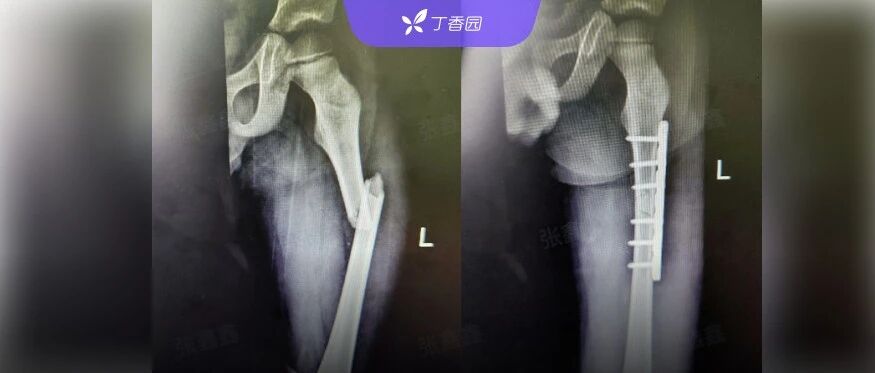

74 岁女子「怀孕」30 多年,一看 CT 惊呆了,主任:极其罕见! 丁香园 · 公众号 · 医学 · 7 小时前 · |